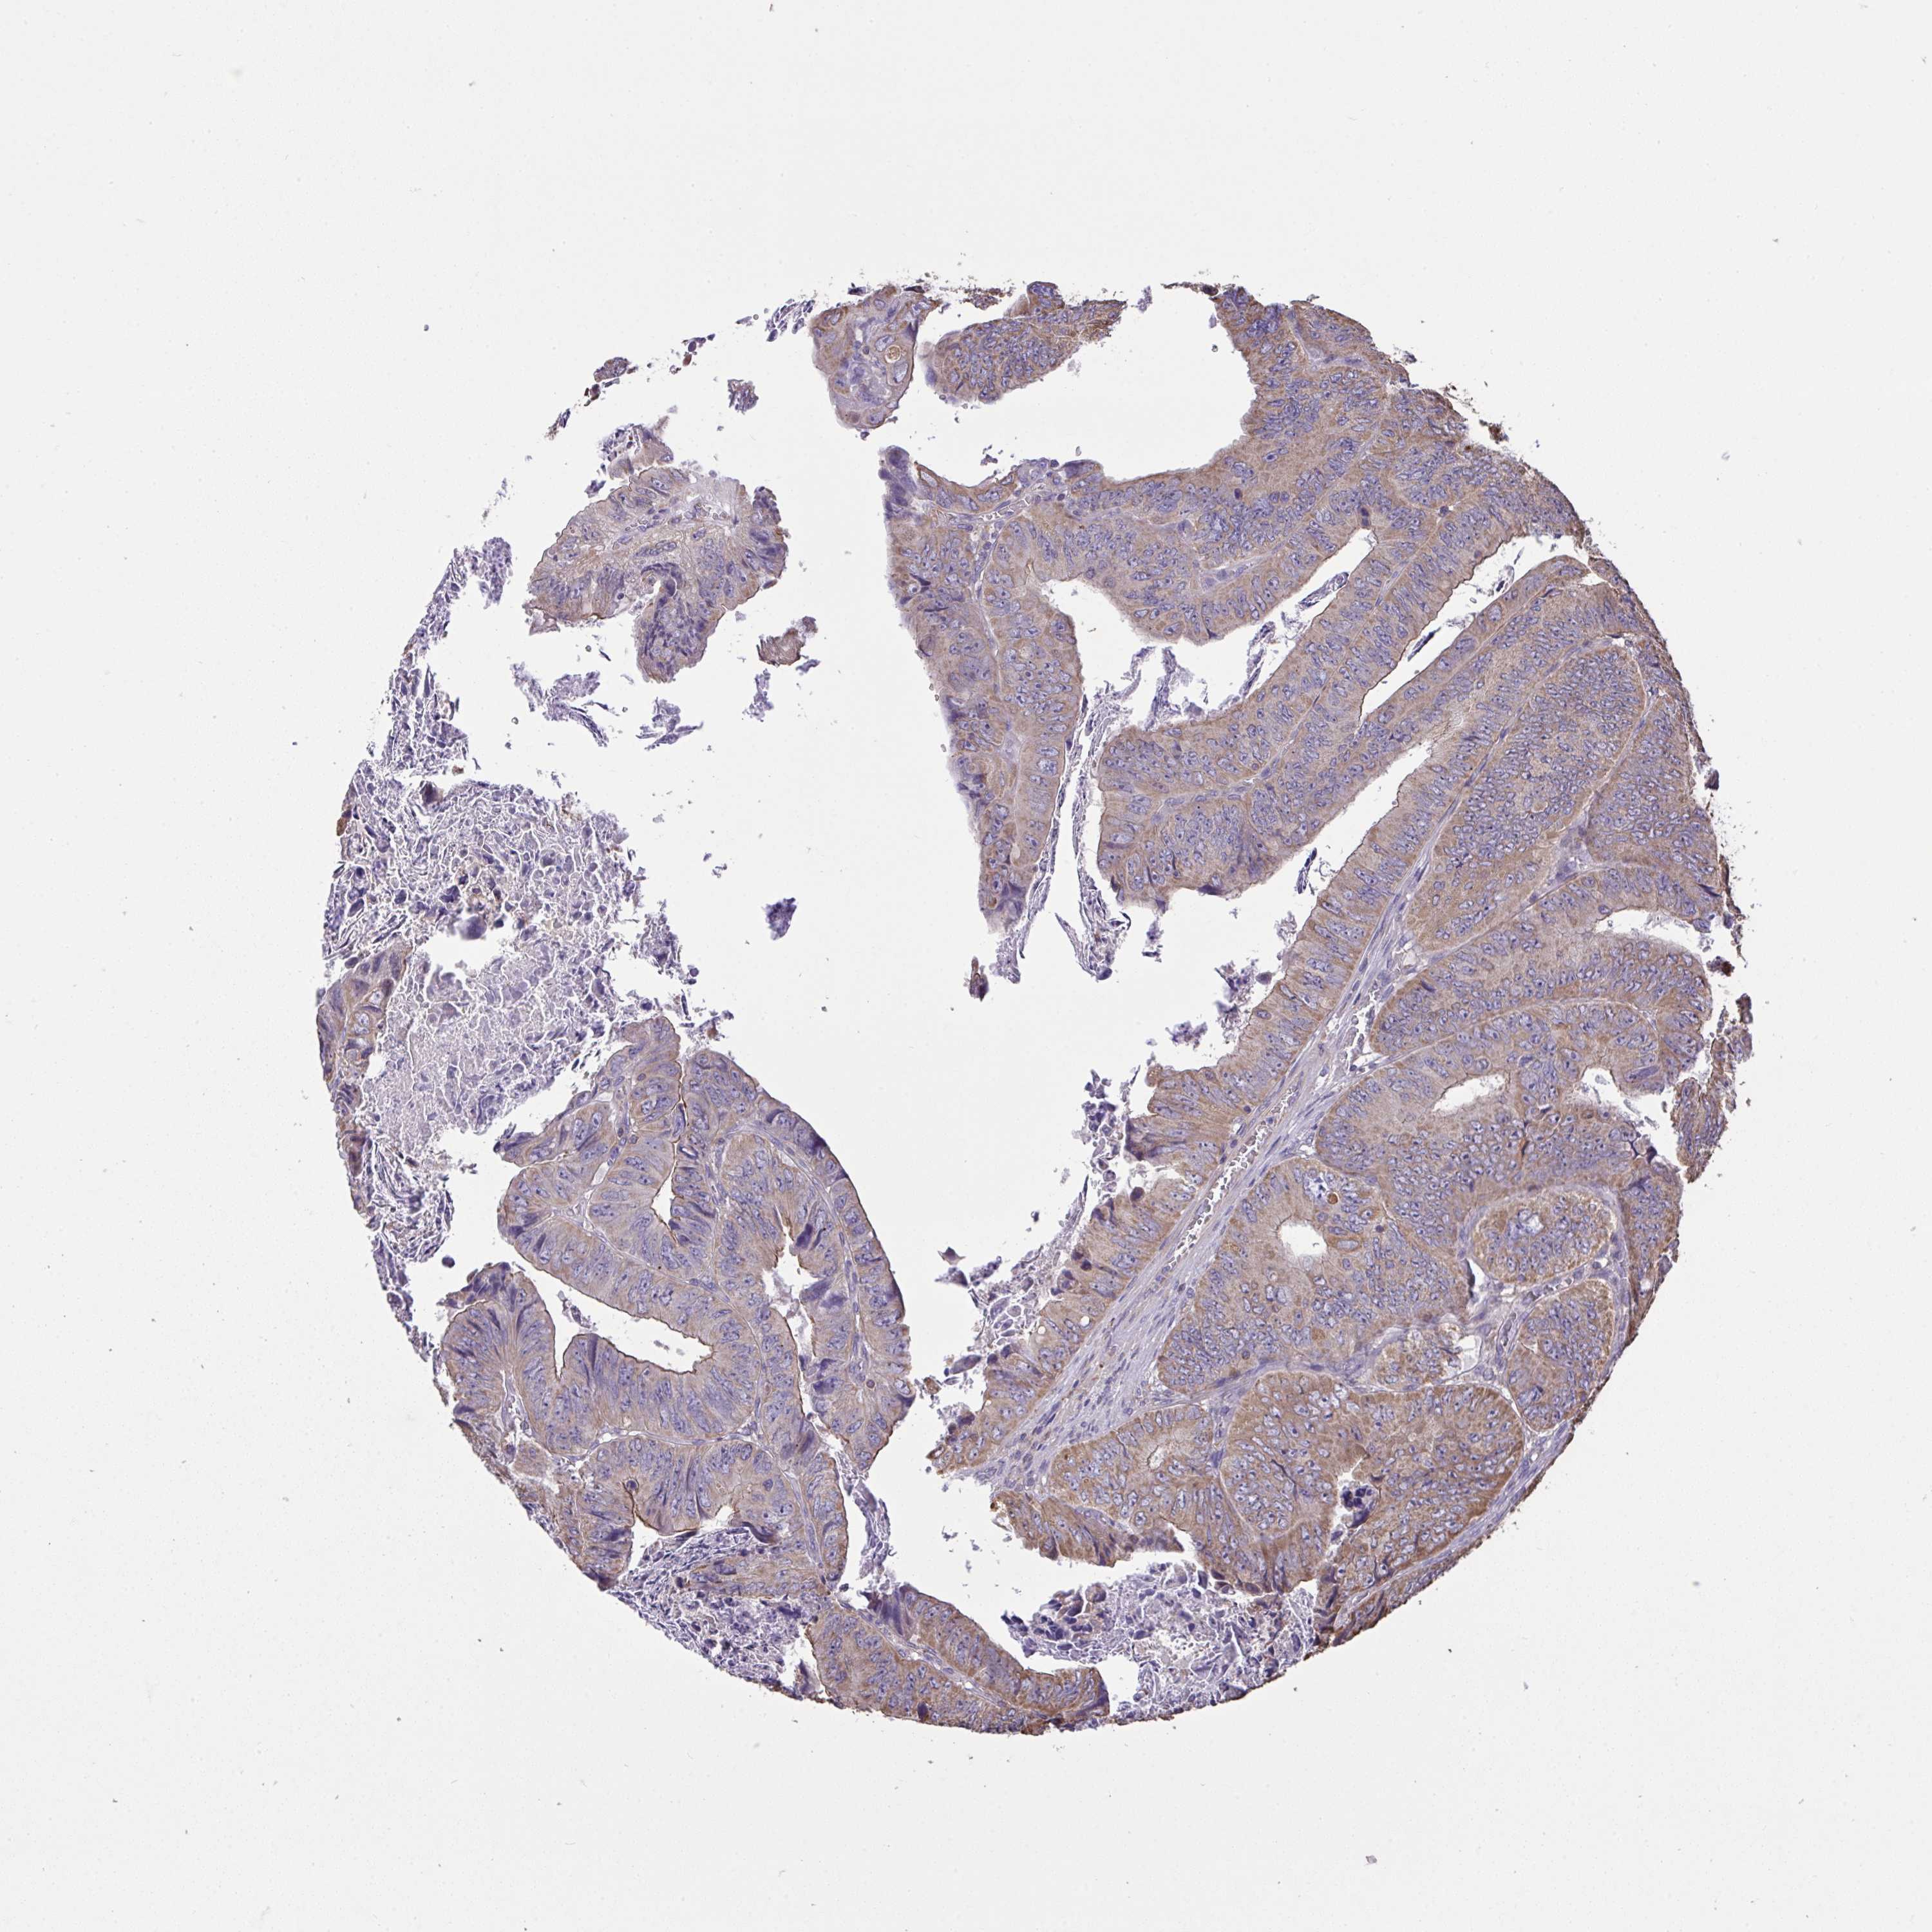

CANCER COLORECTAL CANCER Show tissue menu

Colorectal cancer

Human cancer

Colon adenocarcinoma